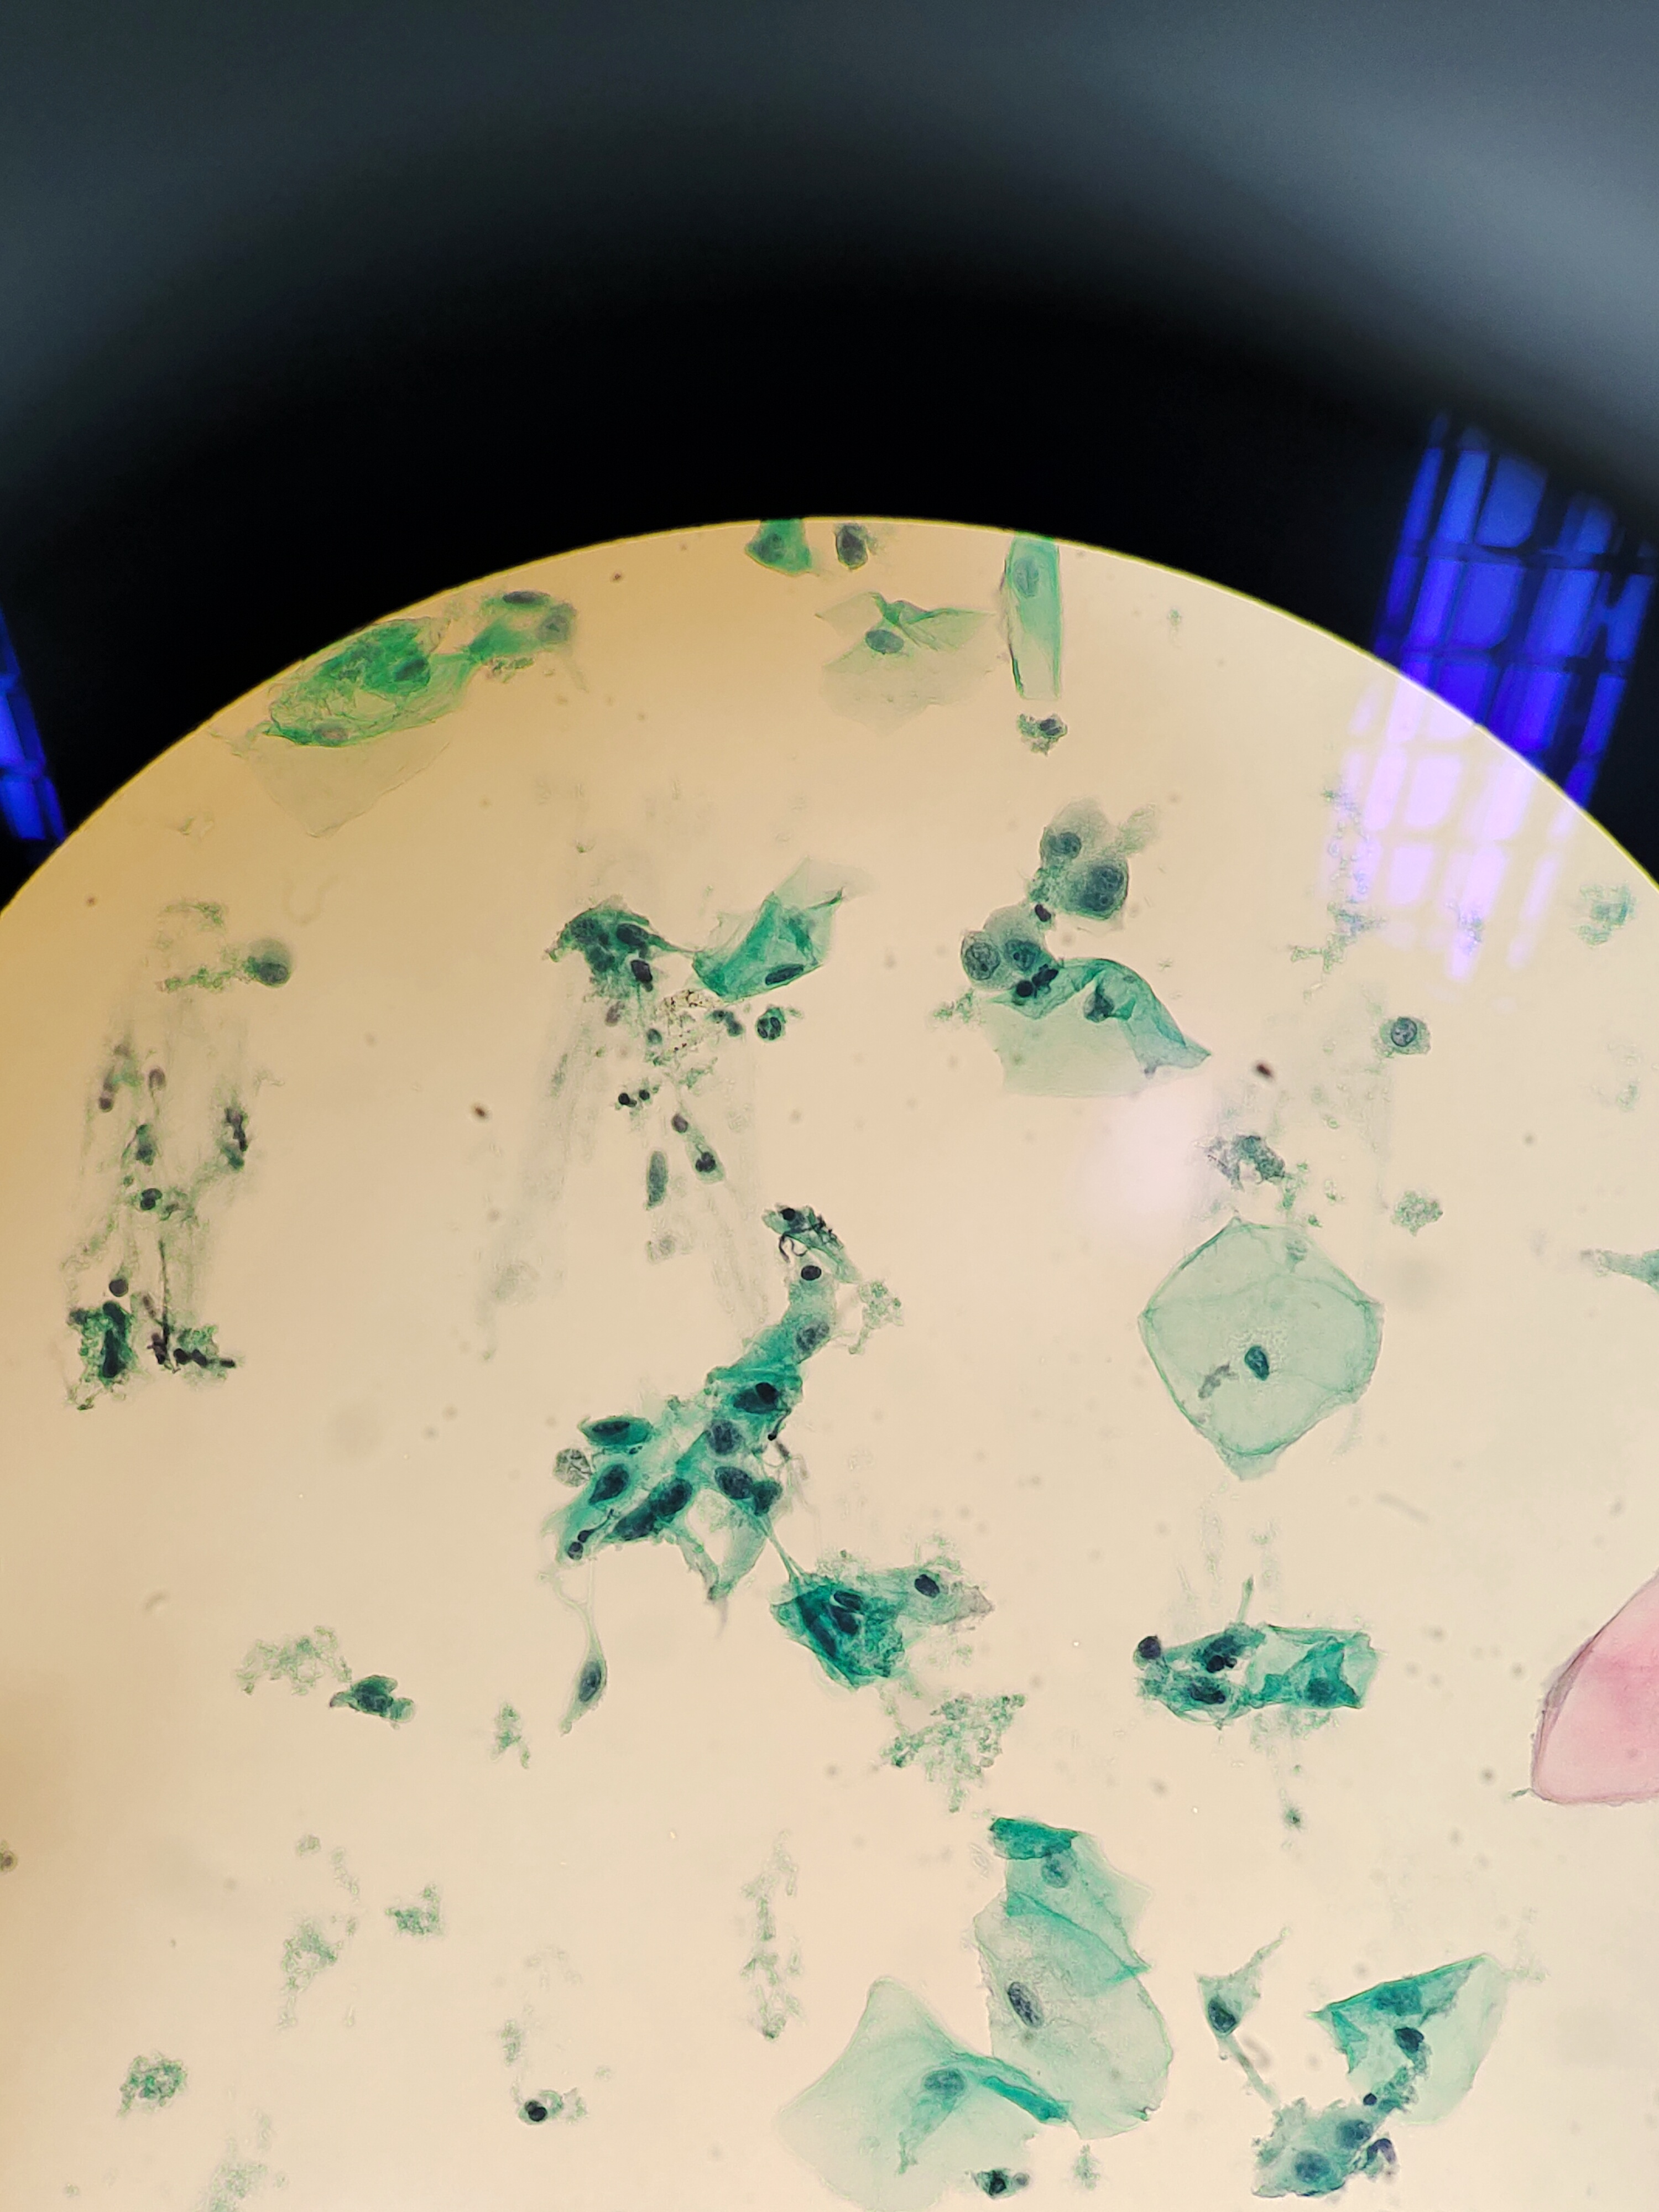

体检来的,HPV阴性。老师们,有些核深染的细胞,有事吗?

宫颈

液基

巴氏

NILM,腺细胞

有化生细胞和腺细胞。

NILM。